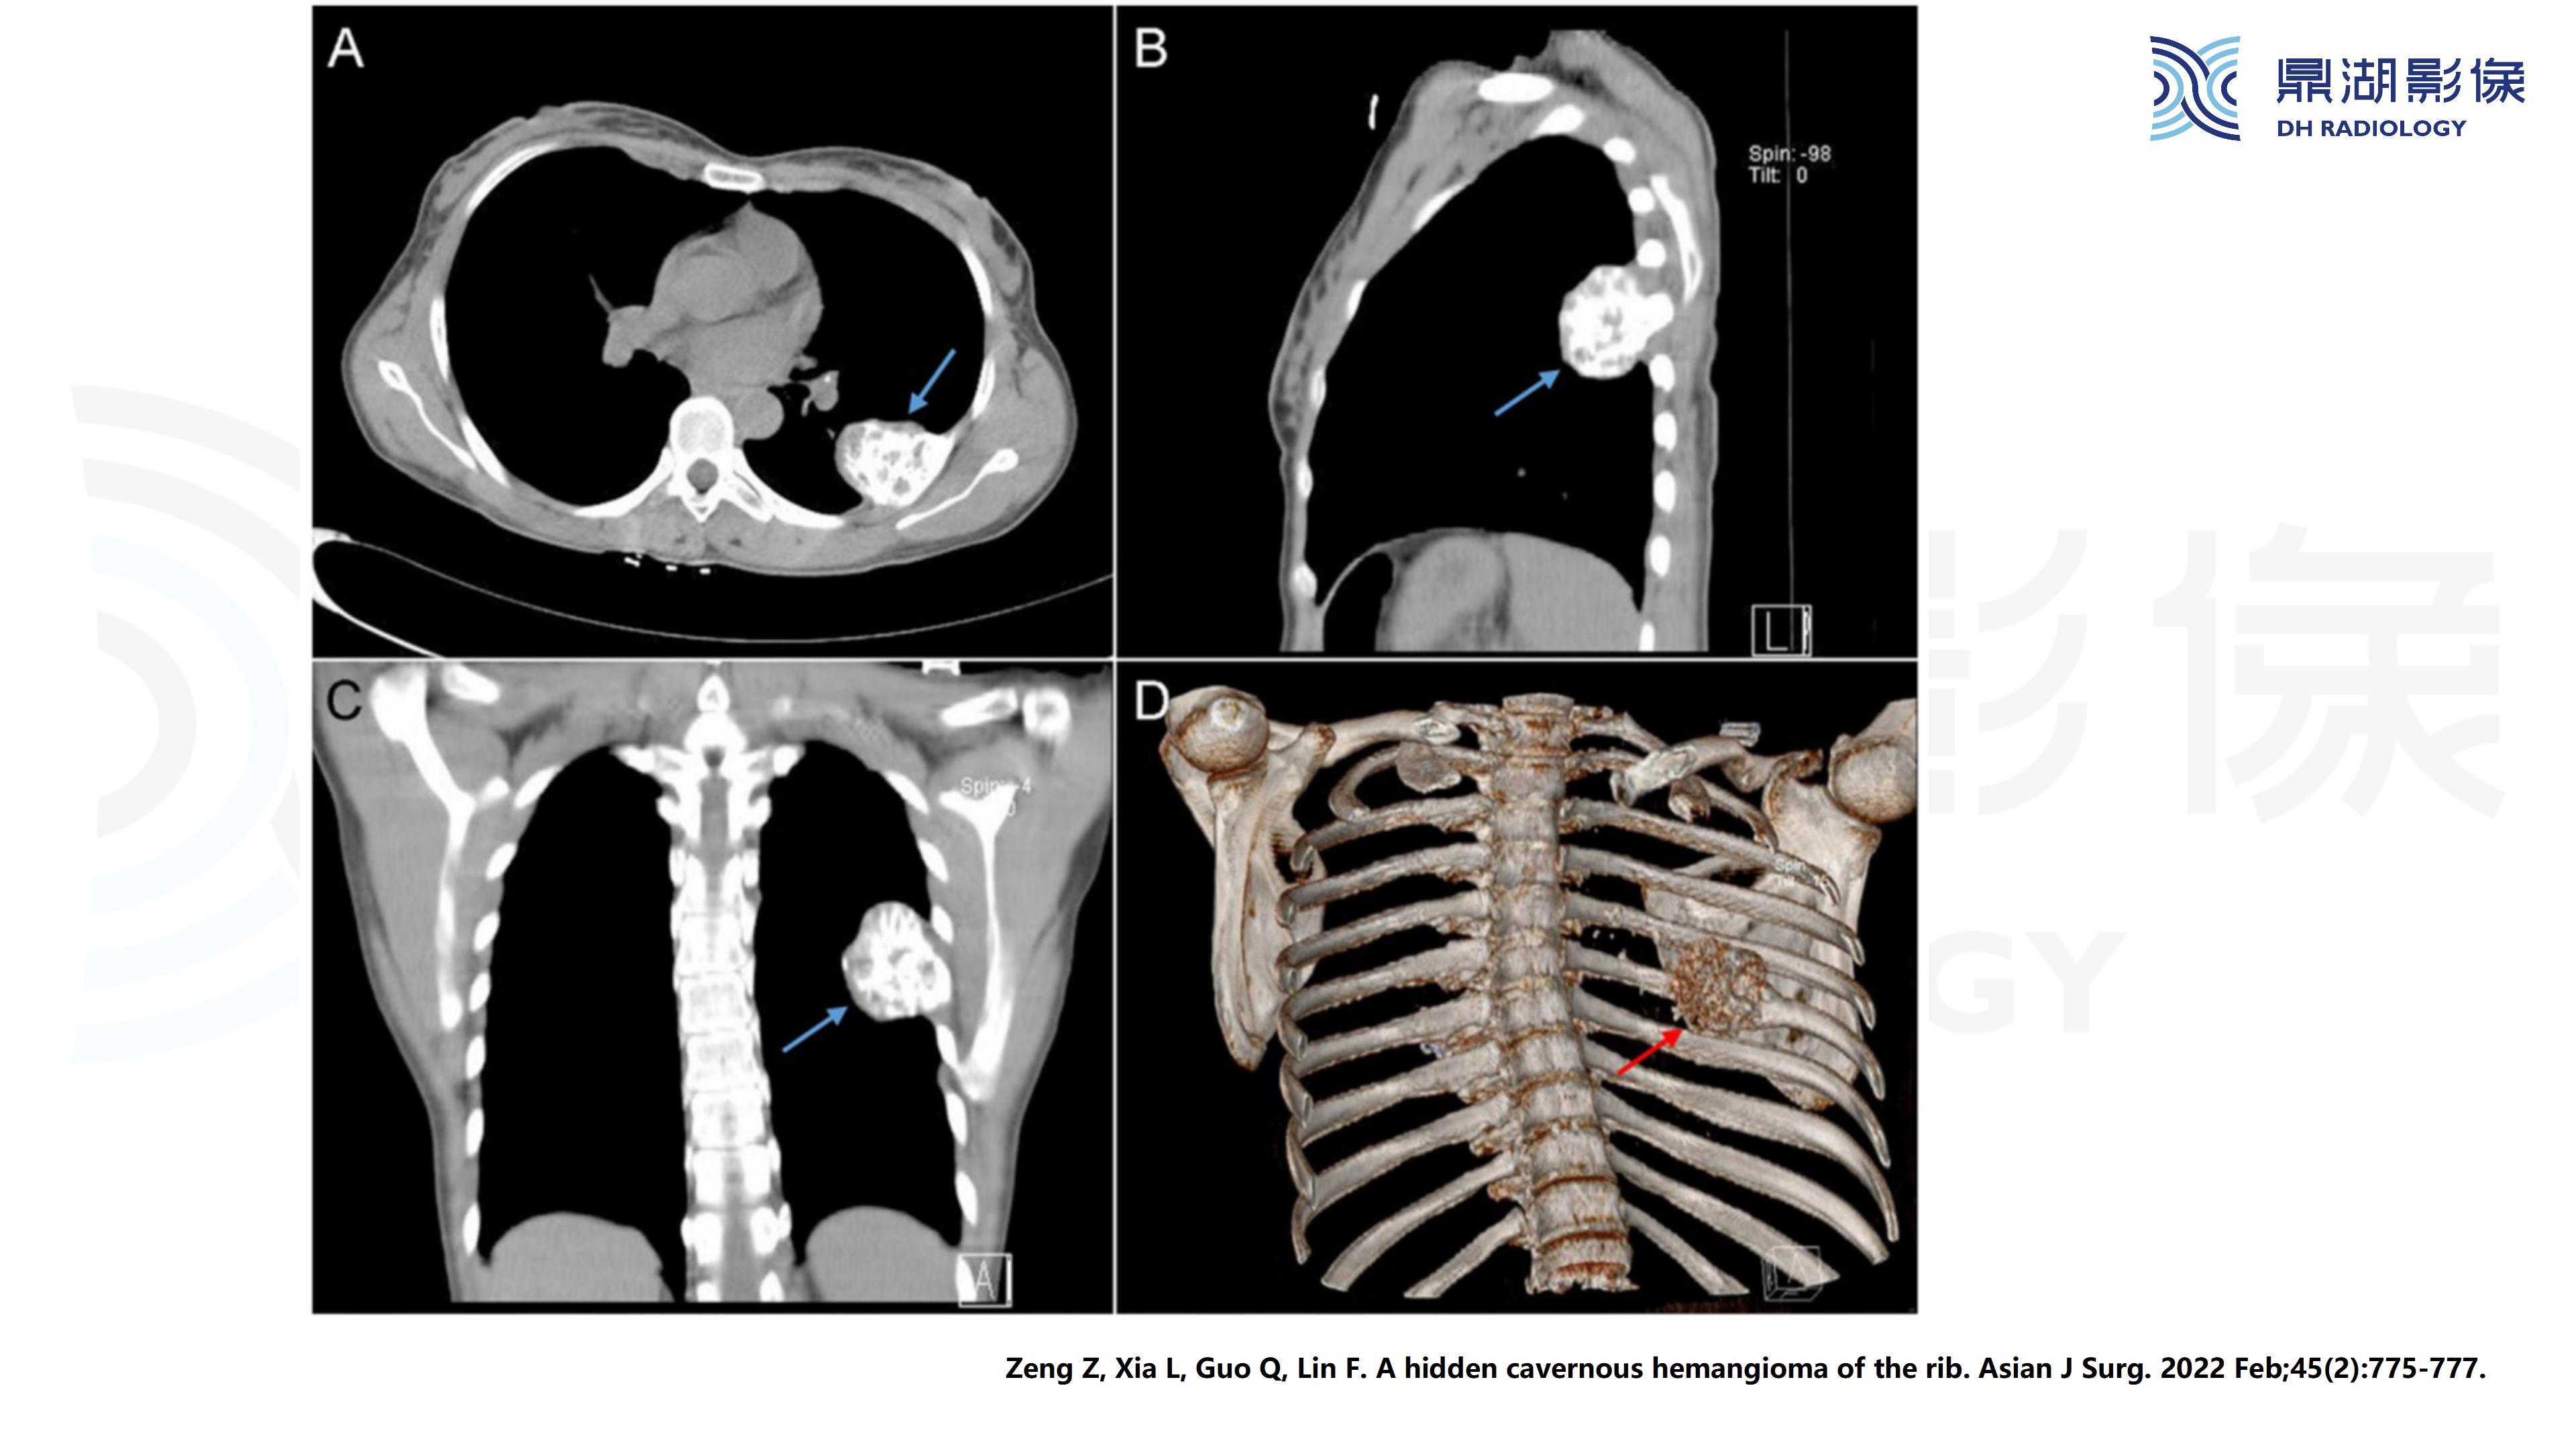

肋骨血管瘤

主诉:发现左侧胸壁局部隆起半年余

现病史:患者女,63岁,半年前活动后出现左侧胸痛,轻度胸闷,无咳嗽咳痰,无头痛头晕,无恶心呕吐,无腹痛等不适。温州大学第一附属医院就诊,未行治疗。半年来左侧胸壁隆起较前明显,活动后轻度胸痛症状,余无明显不适。